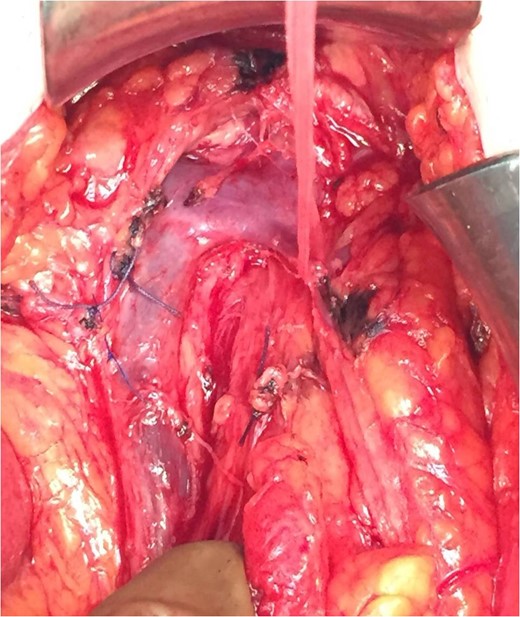

We report, that during dissecting the transverse mesocolon from the greater omentum, and while performing LN dissection around the middle colic vessels, in accordance with the principles of CME, we encountered the following anatomical variability. In this patient, the MCV drained in the splenic vein (Fig. 1). With respect of this rare anatomic variability, CME was completed without hemorrhage (Figs 1 and 2).

It is depicted the principal finding of our case, the anatomic variation of the middle colic vein draining to splenic vein.